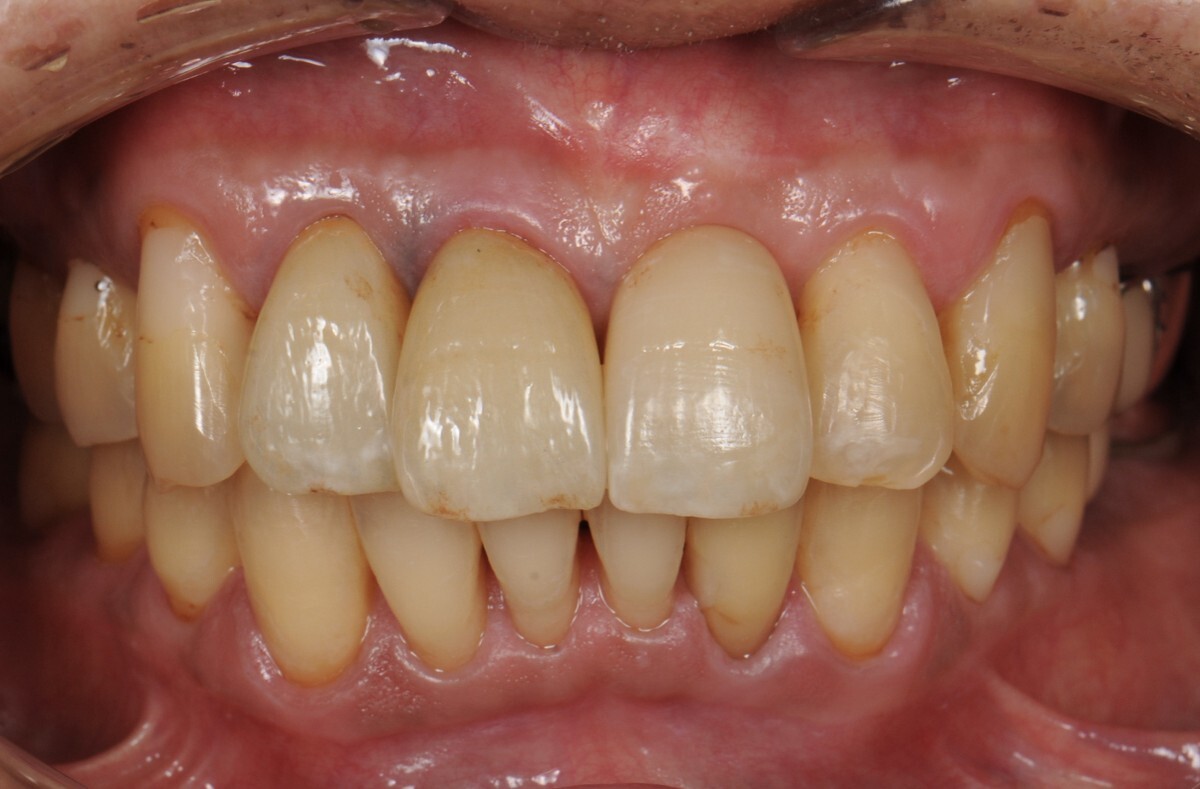

case4 症例(セラミッククラウン前歯)

治療前

治療後

| 費用(税込み) | 1本あたり154,000円×5本 |

|---|---|

| メリット・デメリット | デメリット 歯質を削合する必要がある |

| 治療回数 | 20回 |

| 主訴 | 歯の形態をきれいにしたい |